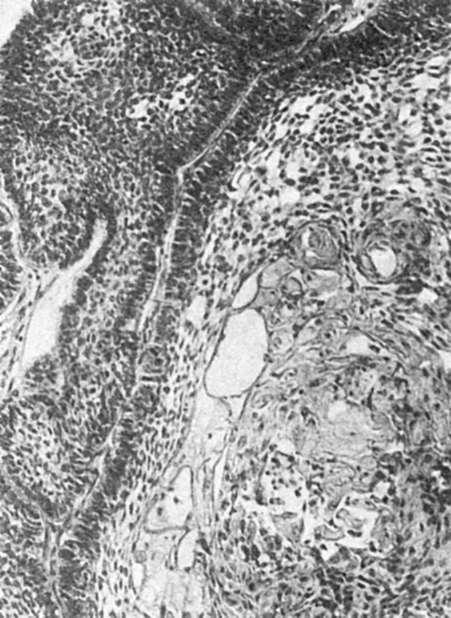

Рис. 359. Фолликулярная

амелобластома

Амелобластома - доброкачественная опухоль с выраженным местным деструирующим ростом. Это самая частая форма одонтогенной опухоли. Для нее типична многоочаговая деструкция кости челюсти. Более 80% амелобластом локализуется в нижней челюсти, в области ее угла и тела на уровне моляров. Не более 10% опухолей локализуется в области резцов. Опухоль чаще всего проявляется в возрасте 20-50 лет, но иногда бывает и у детей. Растет опухоль медленно, в течение нескольких лет. У мужчин и женщин она встречается с одинаковой частотой.

Выделяют две клинико-анатомические формы - кистозную и солидную; первая встречается часто, вторая - редко. Опухоль представлена или плотной белесоватого цвета тканью, иногда с буроватыми включениями и кистами, или множеством кист. Гистологически выделяют фолликулярную, плексиформную (сетевидную),

акантоматозную, базально-клеточную и гранулярно-клеточную формы. Наиболее частыми

вариантами являются фолликулярная и плексиформная формы. Фолликулярная амелобластома состоит из островков округлой или неправильной формы, окруженных одонтогенным цилиндрическим или кубическим эпителием; в центральной части состоит из полигональных, звездчатых, овальных клеток, образующих сеть (рис. 359). В результате дистрофических процессов в пределах островков нередко образуются кисты. Структура этой формы амелобластомы напоминает строение эмалевого органа. Плексиформная форма опухоли состоит из сети тяжей одонтогенного эпителия с причудливым ветвлением.